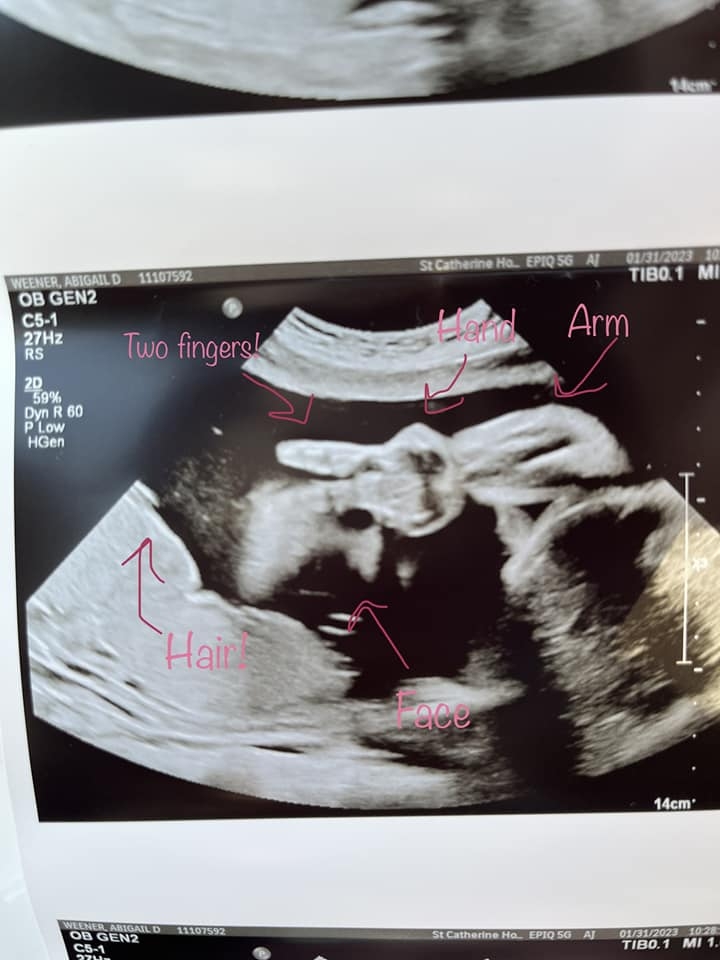

網民們一方面讚照片很奇妙,也有人質疑照片的真實性。Kyle之後有貼出新照片,為Ellie比「Yeah」之前拍攝到,並在照片指出寶寶的臉、頭髮、手指、手臂。Kyle補充醫護人員是拍到這張照片想要趕快擷取,才機緣巧合拍到寶寶比「Yeah」的畫面。拍到照片的一刻,醫護人員立即望著夫婦二人,隨即哄堂大笑,Kyle回憶說:「工作人員說他們以前從未見過這樣的事情」。對Kyle這位準爸爸說,也正好提醒他上帝正在妻子的肚內建造小生命。